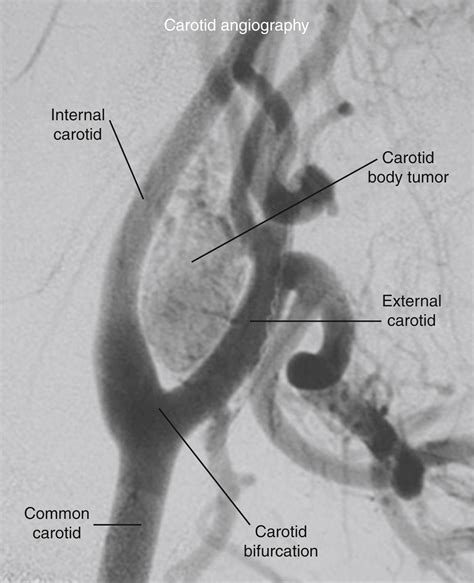

Diagnosing a Carotid Body Tumor requires a combination of physical examination and advanced imaging studies. When a physician suspects such a growth, they typically use specific diagnostic tools to differentiate it from enlarged lymph nodes or other neck masses. The “Lyre sign,” seen on imaging, is a classic finding where the internal and external carotid arteries are splayed apart by the tumor mass.

Catheter Angiography The "gold standard" for identifying the blood supply and planning potential embolization.